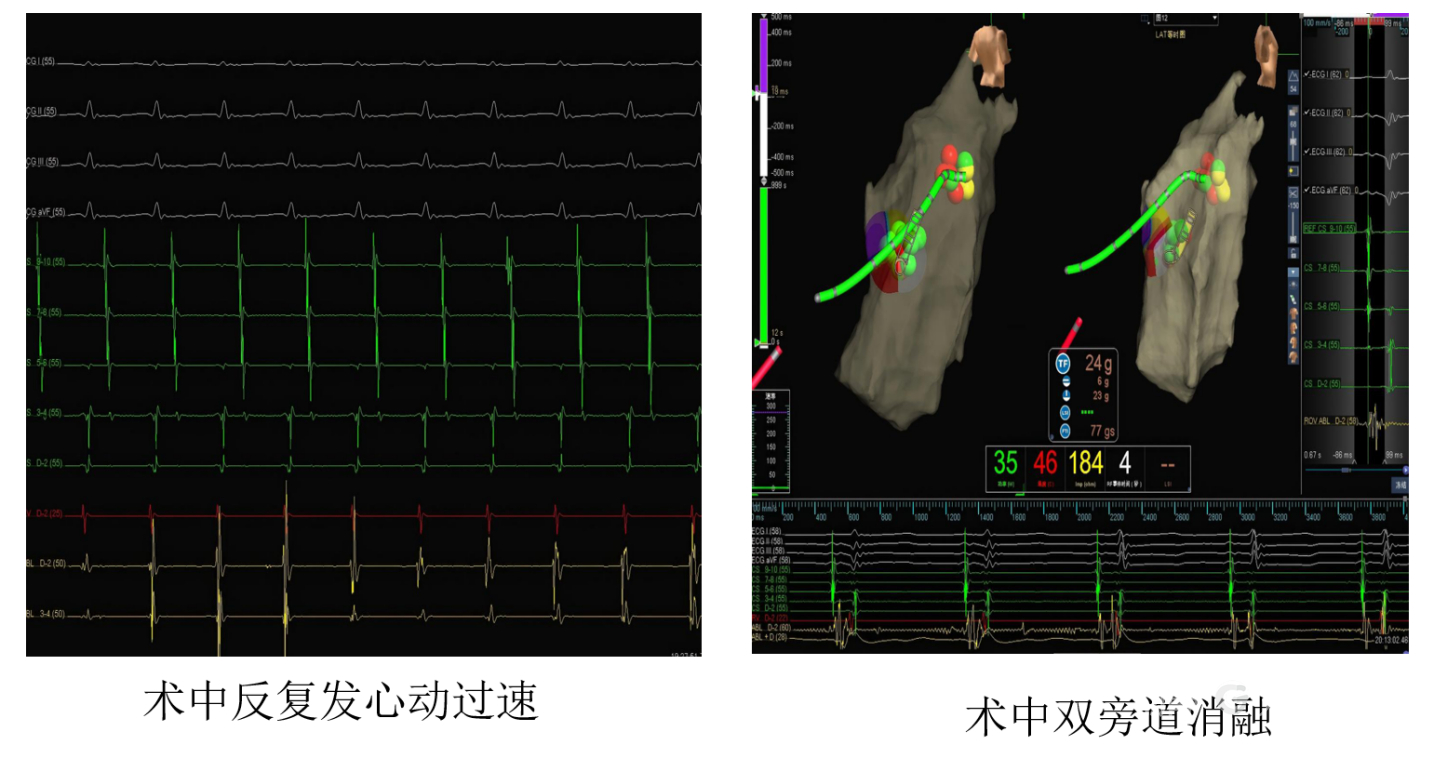

接着,心内科医生在心脏完全暴露、直视可见的情况下,沿着三尖瓣环进行精细的“地图绘制”(医学上叫激动标测)。借助先进的三维标测系统和清晰的直视视野,他们准确找到了那两条异常电路,尤其是藏在“小口袋”深处的那条危险电路,并顺利实施了射频消融——用热能精准“烧断”了这两条“短路”的“电线”。

更棘手的是,患者有两条“异常电路”,其中一条正好藏在上文提到的那个“小口袋”的深处。这个位置极其刁钻,如果采用传统的微创介入手术(从大腿血管伸入导管),导管根本够不着、贴不稳,消融成功率很低,复发风险很高。